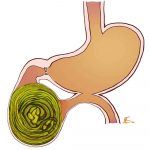

Bezoars là loại u lành cấu tạo bởi những vật lạ nuốt vào như tóc (thói quen nuốt tóc, bệnh tâm thần), thực vật (trái cây, rau loại có nhiều sợi xơ rắn, dài, đọng thành khối).Khối u có thể sinh ra khi nuốt 1 lần rất nhiều hay nuốt dần dần, lâu ngày di chuyển xuống tá tràng, tiểu tràng hay manh tràng và mắc lại trên một đoạn ruột bị hẹp từ trước…